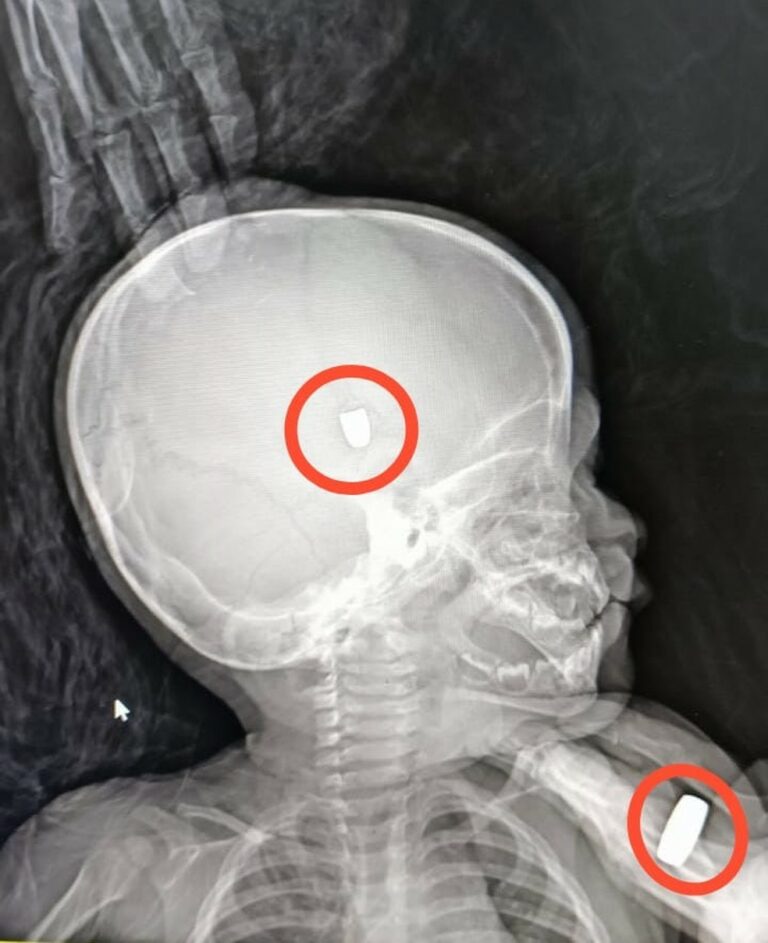

“A criança chegou conduzida pelo Samu. Foram feitas todas as manobras, todos os procedimentos, inclusive a intubação da criança. ApĂłs isso, como a lesĂŁo foi no crĂąnio e a bala ficou alojada, entramos em contato com o Hospital JoĂŁo Paulo II, em Porto Velho, pois no hospital em Ariquemes nĂŁo temos neurocirurgiĂŁo. ApĂłs estabilizarmos o bebĂȘ, ele foi transferido para a capital”, disse Tiago Lima.

Segundo informaçÔes da Secretaria de Estado da SaĂșde (Sesau), a criança passou por cirurgia na manhĂŁ desta terça-feira (11) e estava sendo transferida para uma UTI do Hospital Cosme e DamiĂŁo.

Durante a tarde, a Sesau informou que o estado de saĂșde da criança Ă© grave. Ela estĂĄ entubada e mantida sob assistĂȘncia da equipe multidisciplinar.